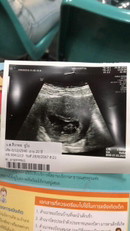

คุณแม่รออีกสัก1_2อาทิตนะค่ะ แม่บ้านนี้คุณหมอทาง รพ คอนเฟริมว่าตั้งครรภ์ไข่ปลาอุเช่นกันค่ะ และแม่บ้านนี้กับไปตามนัดที่ทาง รพ.แจ้งมา สรุปมีตัวอ่อนค่ะ เหตุการไข่ปลาอุวันนั้นจนวันนี้แม่บ้านนี้ตั้งครรภ์ได้7เดือนแล้วค่ะ แม่อยากแนะนำให้ไป รพ เฉพาะทางสูตินารีเวช โดยตรงจะดีกว่านะค่ะคุณแม่